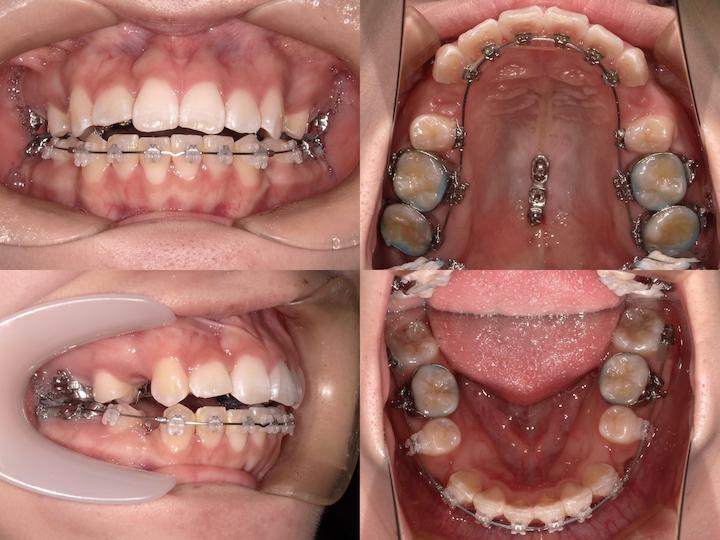

症例概要

本症例は、叢生および口唇部の突出感を主訴とする患者様に対し、ハーフリンガル矯正装置(上顎舌側・下顎唇側)を使用して治療を行いました。

下顎骨の後方位を伴うハイアングル症例であったため、上顎大臼歯の圧下を治療計画に組み込み、下顎骨のアンチクロックワイズローテーション(反時計回り回転)を誘導することで、口唇部の突出感改善と良好な咬合関係の確立を目指しました。

初診時の口腔内所見および頭部X線規格写真分析より、以下の所見が認められました。

・上下顎前歯部の叢生

・口唇部の突出感

・AngleⅠ級臼歯関係(良好な臼歯関係)

・下顎骨の後方位(ハイアングル症例)

・下顎下縁平面角の増大

ハーフリンガル矯正装置を採用し、上顎は舌側矯正装置(リンガルブラケット)、下顎は唇側矯正装置(ラビアルブラケット)を使用しました。

・i-station(歯科矯正用アンカースクリュー)の植立:正中口蓋縫合部に植立し、上顎大臼歯の固定源として使用

・上顎大臼歯の圧下:i-stationからの圧下力により、上顎大臼歯を垂直的に圧下

・上顎大臼歯の固定:抜歯スペース閉鎖時の近心移動を防止し、AngleⅠ級臼歯関係を維持

・フルサイズワイヤーの使用:.018×.025インチTMA(チタンモリブデン合金)ワイヤーを使用し、臼歯部のみが選択的に圧下するように設計

・パラタルバーの装着:上顎大臼歯の幅径を維持し、歯列弓形態の安定を確保

治療結果

上顎大臼歯の圧下により下顎骨のアンチクロックワイズローテーションが誘導され、口唇部の突出感は著明に改善されました。

また、叢生も解消され、AngleⅠ級臼歯関係を維持したまま、機能的かつ審美的に優れた咬合状態を獲得することができました。

臼歯部の咬合も良好に保たれ、患者様からも高い満足度をいただいております。